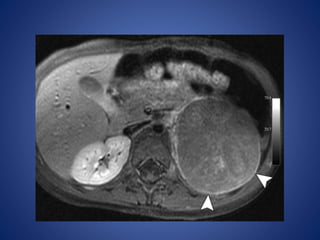

At CT, large ACNs show heterogeneous, predominantly peripheral

enhancement.

The tumor may be surrounded by a thick, capsule-like rim that

enhances. Fine or coarse calcification is seen at CT in about 30% of

cases

• #38 ACN in an 18-month-old boy with isosexual precocious puberty and Cushing syndrome. Postcontrast: shows the tumor with an enhancing rim (arrowheads).

• #39 Coronal reformatted CT image shows the left adrenal mass (arrowhead) with enhancing bands in a radiating or stellate arrangement (arrows). Coronal fused positron emission tomographic (PET)/CT image shows increased metabolism in the tumor (arrowhead)